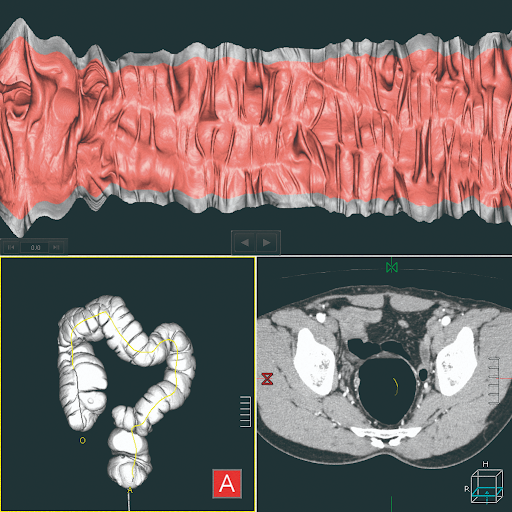

Визуализация толстой кишки

Используя программное обеспечение автоматической визуализации и инструменты отчетности, программное обеспечение Colon View обеспечивает точную диагностику при обследовании толстой кишки. Инновационные MPR и Fly Through Fusion позволяют точно оценить объем опухоли в толстой кишке.